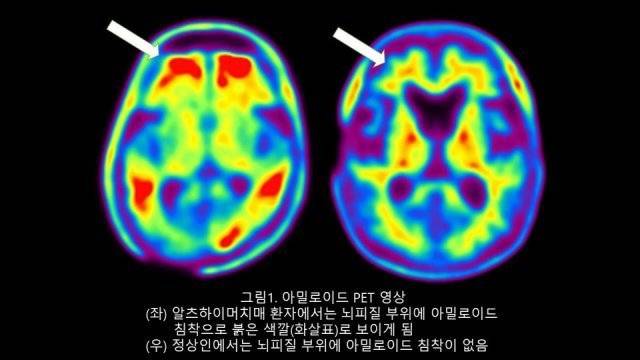

기존 방식인 아밀로이드 양전자 방출 단층 촬영(PET-CT) 검사 또는 뇌척수액 검사는 비용이 많이 들며 시간도 오래 걸린다. 치료 현장에서 간편하게 활용할 수 없다는 얘기다.

알츠하이머병은 아밀로이드 베타(Amyloid beta)라는 단백질이 뇌에 축적되어 플라크를 형성하고, 타우(Tau) 단백질이 엉키는 게 특징이다.